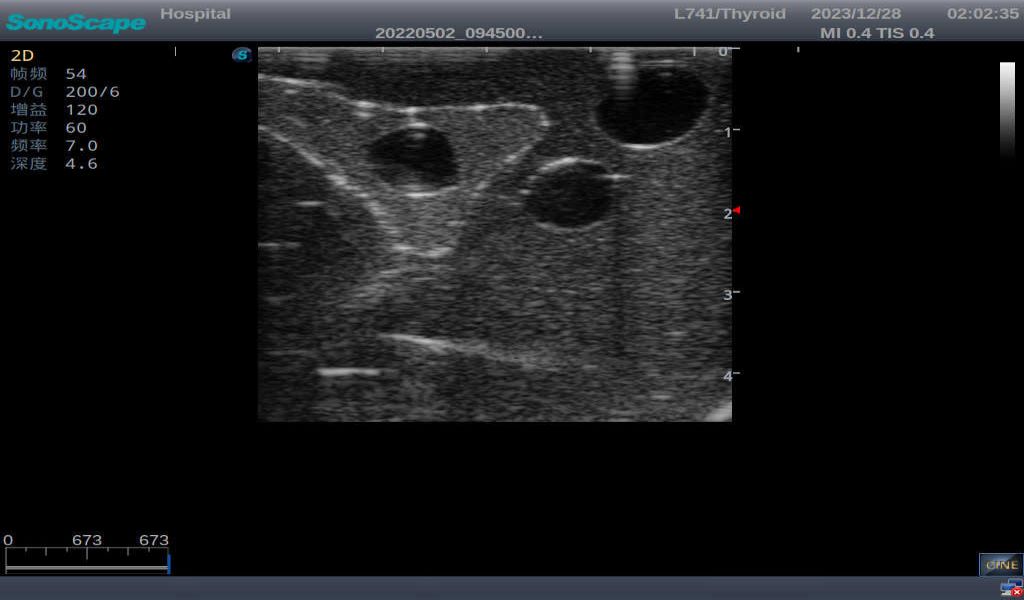

2)       Ultrasonically realistic materials at neck & various types of real ultrasonic machines in clinical available, developing realistic imaging like common carotid artery, internal jugular vein, trachea, thyroid cartilage, cricoid cartilage, lobes of thyroid gland and isthmus

3)       It comes with four (4) thyroid modules and can show five (5) ultrasonic images: normal thyroid, thyroid adenoma, thyroid cancer, nodular goiter, thyroid cyst

Thyroid cyst, which fluid area, dark and echo-free area can be seen